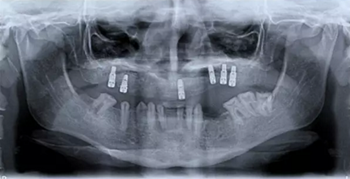

該患者 12 歲時(shí)已診斷為釉質(zhì)發(fā)育不全。家族史正常,否認(rèn)全身系統(tǒng)性疾病。全身系統(tǒng)檢查無明顯異常,檢查雙側(cè)顳下頜關(guān)節(jié)、開口度正常??趦?nèi)及 X 片檢查見上頜縮窄,上頜牙列缺失,安氏三類錯(cuò)牙合,下頜牙牙冠短小,牙根正常。上頜大量牙槽骨因以前手術(shù)干預(yù)而喪失,后牙區(qū)牙槽骨高于前牙區(qū)。病變牙齒在之前的治療中已被拔除。

圖 2. 曲面斷層片(術(shù)前、拔牙后、種牙后)